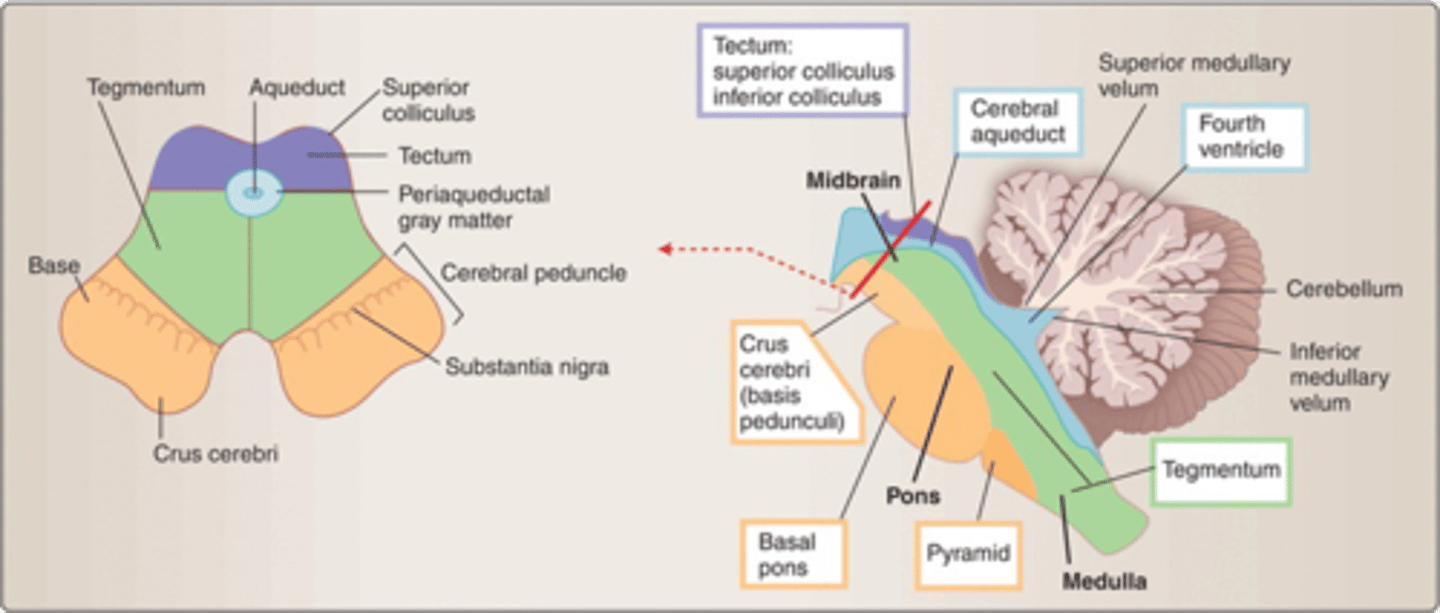

what are the 4 areas that the brainstem can be divided into (from posterior to anterior)?

1. tectum

2. ventricular system

3. tegmentum

4. basal portion

which area of the brainstem is the roof over the ventricular system?

tectum

which area of the brainstem makes up the core of the brainstem?

tegmentum

which area of the brainstem is situated most anteriorly?

basal portion

which region of the brainstem contains the cerebral penduncles? what is the ventral portion of the cerebral peduncles that contain corticospinal and corticobulbar fibers?

midbrain; crus cerebri

which region of the brainstem contains the cerebral aqueduct?

midbrain

looks like a hole in the center of the midbrain

cerebral aqueduct connects the 3rd and 4th ventricles

what are the 2 components that make up the ventral and dorsal area of the pons?

1. basilar pons (ventral)

2. tegmentum (dorsal)

what component of the pons forms the floor of the fourth ventricle?

tegmentum

what region of the brainstem contains the cerebellar peduncles (to connect the cerebellum to the brainstem)?

pons

what medulla structure is a swelling along the ventral surface composed of motor fibers of corticospinal and corticobulbar tracts?

pyramid